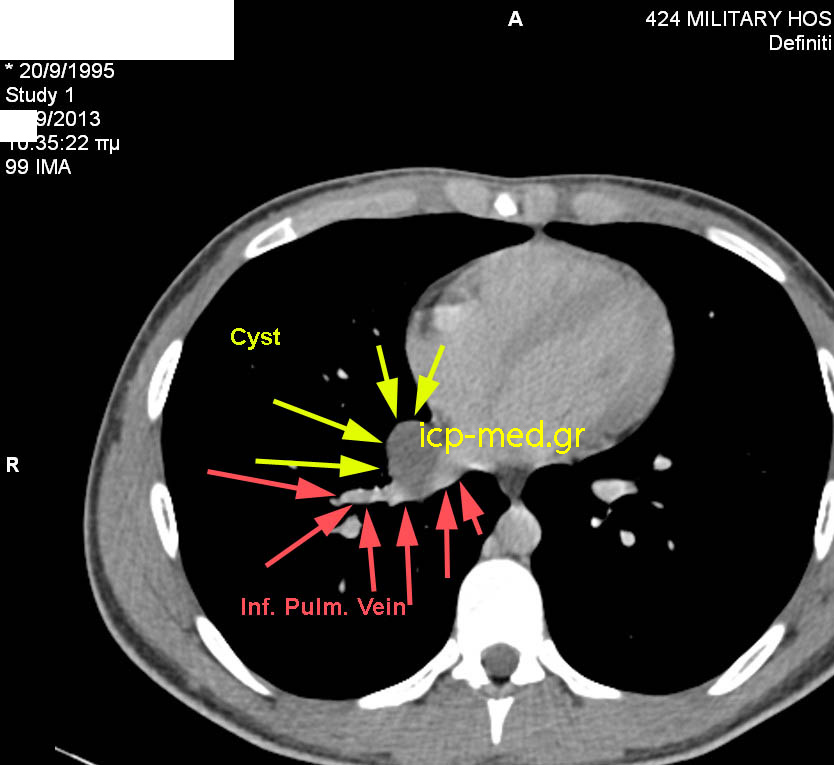

Βρογχογενής Κύστη Μεσοθωρακίου Δεξιά

CT: Στενή ανατομική σχέση κύστεως με Κάτω Πνευμονική Φλ (ΕΡΥΘΡΑ)